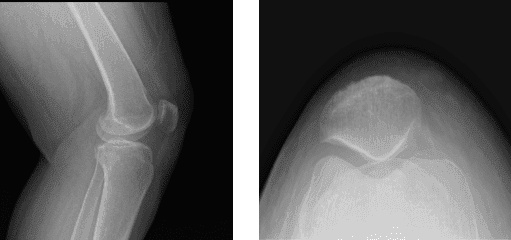

Los resultados de las radiografías presentados y revisados mostraron que no existen enfermedades degenerativas. Aconsejaron al paciente que se sometiera a una resonancia magnética y descubrí que hay edema subcutáneo tanto anterior como anteromedial.

Sospecha de desgarro en el cuerno posterior del menisco medial. Hay una señal oblicua muy tenue que parece extenderse hasta la superficie articular inferior. Se observó una ruptura parcial del LCP proximal y también se observaron condromalacia leve de rótula y bursitis infrapatelara profunda.

Radiografía de la rodilla izquierda completa con rótula

MRI-3T Rodilla Izquierda sin contraste